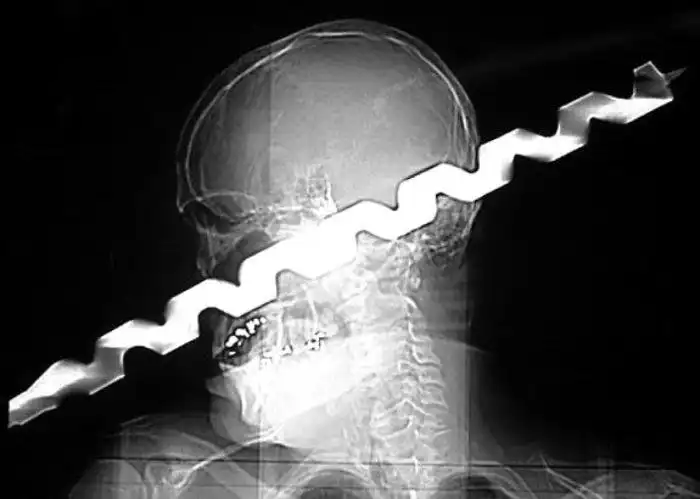

Необычные предметы в теле людей на рентгеновских снимках

На рентгеновских снимках людей порой можно обнаружить самые необычные предметы, которые находятся в их теле.

Человечество явно с гвоздями не дружит!!! Что не снимок то гвоздь в башке!